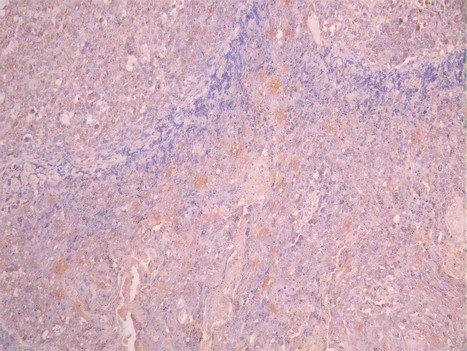

• IHC image of CSB-RA957044A0HU diluted at 1:100 and staining in paraffin-embedded human cervical cancer performed on a Leica BondTM system. After dewaxing and hydration, antigen retrieval was mediated by high pressure in a citrate buffer (pH 6.0). Section was blocked with 10% normal goat serum 30min at RT. Then primary antibody (1% BSA) was incubated at 4°C overnight. The primary is detected by a Goat anti-rabbit polymer IgG labeled by HRP and visualized using 0.05% DAB.